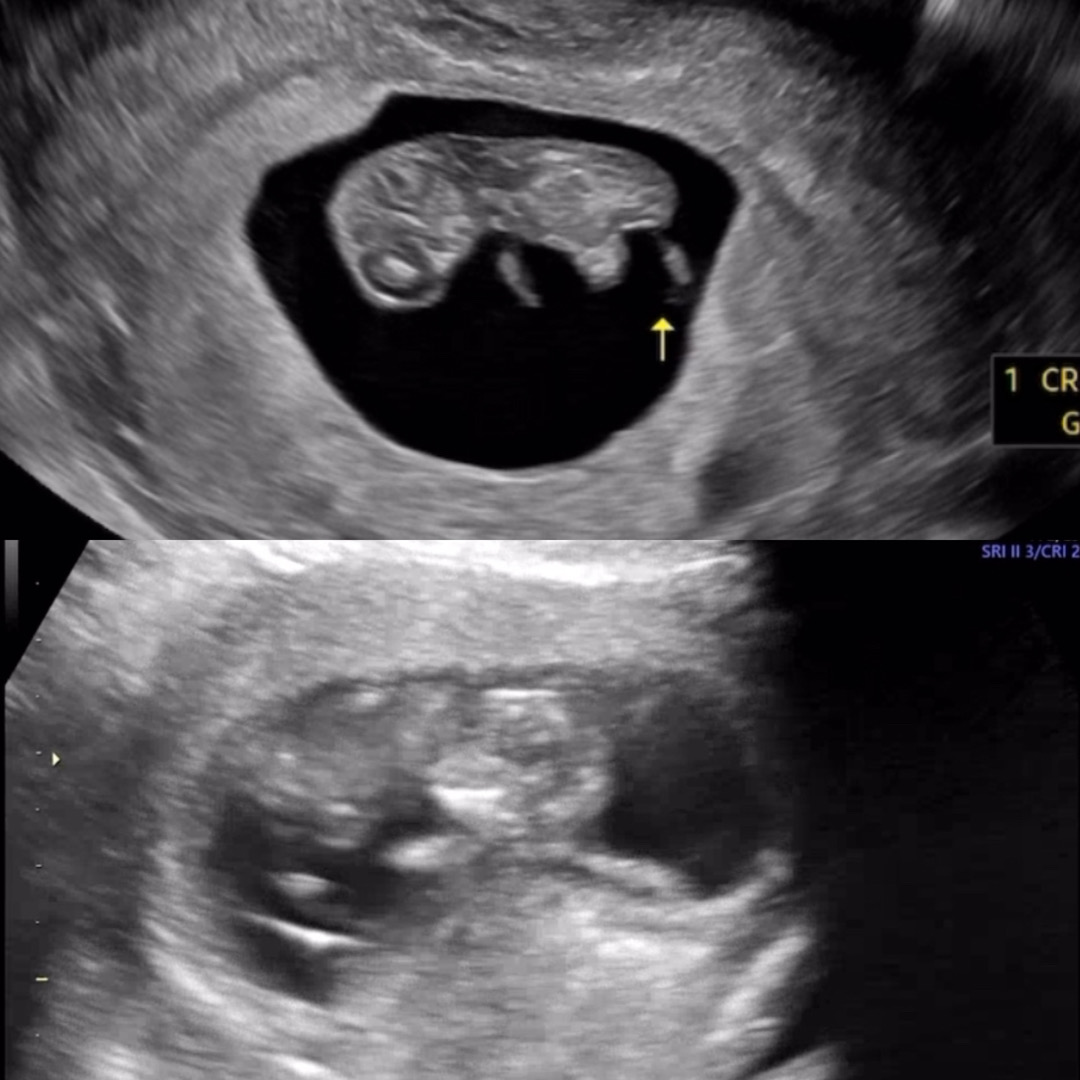

초음파 볼때 아기집 크기가 다르게 보이는 분 계신가요? 서브병원에서 볼때 진짜 커보였는데 오늘 분만 병원 진료 보러갔는데 조금 작게 보여서요ㅎㅎ 보는 각도에 따라 다른건가...아기는 잘 크고 있는데 피고임은 없는데 안정기까지 질정 넣기로 했어요ㅠㅠ (위-서브6.10/아래-분만6.13)